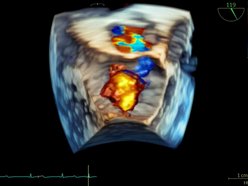

To ogromny krok naprzód. Urządzenie pozwala dokładnie ocenić, jak pracują komory i przedsionki serca, a także szybko uzyskać rzetelne wyniki przy minimalnym wysiłku ze strony operatora – mówi dr Maciej Nadel, kardiolog z Uniwersytetu Medycznego w Łodzi.

Nowy echokardiograf GE Vivid E95 Ultra Edition został wyposażony w specjalną głowicę, która znacząco przyspiesza badania i zwiększa ich dokładność. To szczególnie ważne w kardiologii, gdzie liczy się czas i precyzja. Sprzęt będzie służył zarówno pacjentom trafiającym do specjalistów, jak i naukowcom prowadzącym badania nad nowymi metodami leczenia. To kolejny dowód na to, że łódzka medycyna łączy nowoczesną technologię z troską o zdrowie mieszkańców.